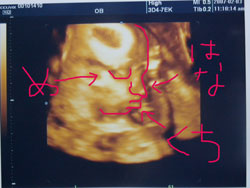

今回の3D↓

分かるかなー???

右向いた横顔

って感ぢなんですけど・・・

遠くから見ると見やすいかも!

やっぱ写真超見づらいですよねェ![]()

縁取りしてみました!!!

これでもダメ??(*´pq`)クスッ

240グラム

に成長してました♪